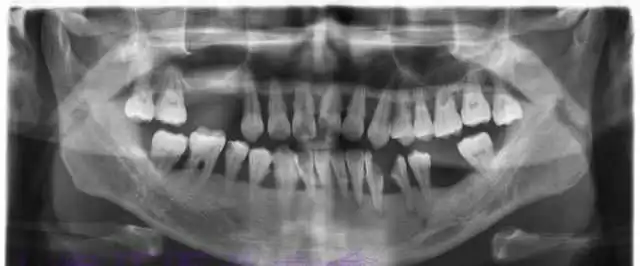

下面这张X光片是比较典型的牙周炎的X光片,该患者全口所有的牙齿都呈现出2~3度的松动。患者现在感觉无法用牙齿咀嚼。坦白地讲,牙周炎发展到这种程度,很多时候医生也束手无策了。为了保留更多的牙槽骨,医生会不得不拔掉那些严重松动的牙齿。